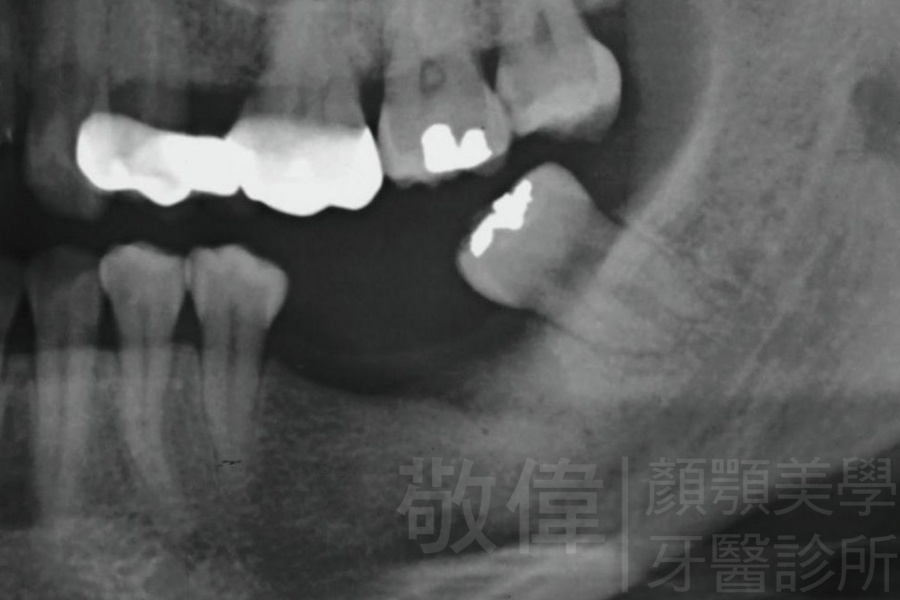

治療前-缺牙區X光   治療後-大臼齒X光